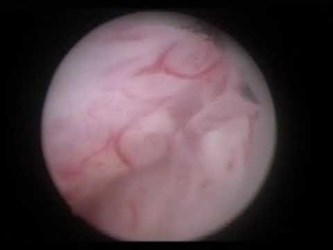

Биполярная энуклеация гиперплазии простаты

Операцию выполняет доктор Сорокин Николай Иванович.